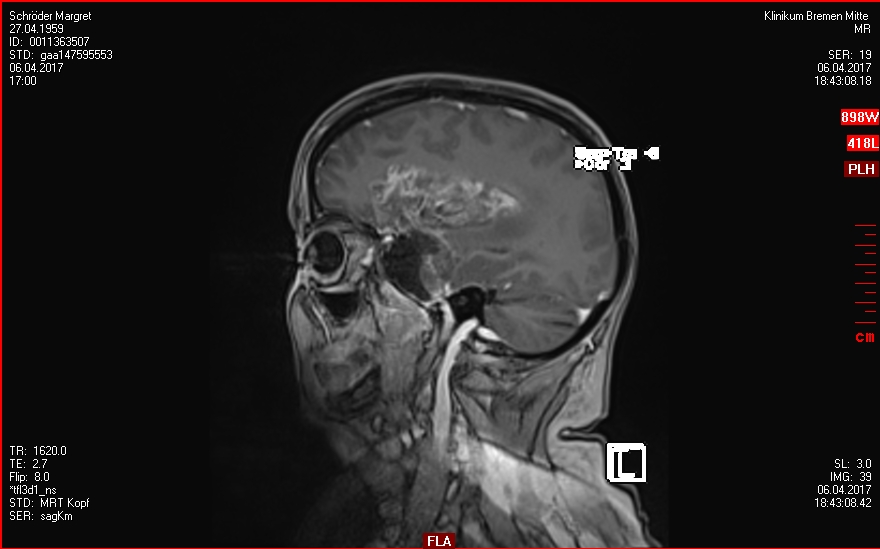

30.03.2017

OP - Krankenhaus Bremen-Mitte

Neurochirugie

Resektion des Keilbeinflügelmeningeoms links